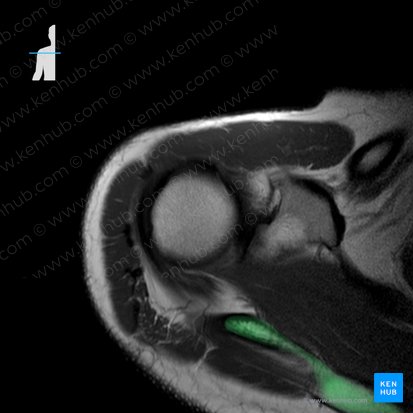

Spine of scapula

The posterior surface of the scapula (or shoulder blade) has a prominent ridge of bone know as the spine of scapula. It is a shelf-like projection that separates the posterior surface of the scapula into two parts: the superior supraspinous fossa and the inferior infraspinous fossa.

The spine of scapula can be readily palpated and serves as an attachment point for several muscles of the scapular region.

Function Divides the posterior surface of the scapula, serves as attachment point for several muscles